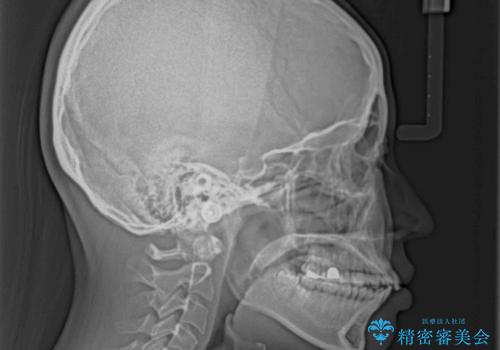

- 前歯が突出して、眠るときに口が開いてしまうことを気にして来院された患者様です。

横から見た際の口元の飛び出した印象も改善したいとのことで、上下左右の第一小臼歯4本を抜歯し、ワイヤー装置にて抜歯矯正を行うこととしました。